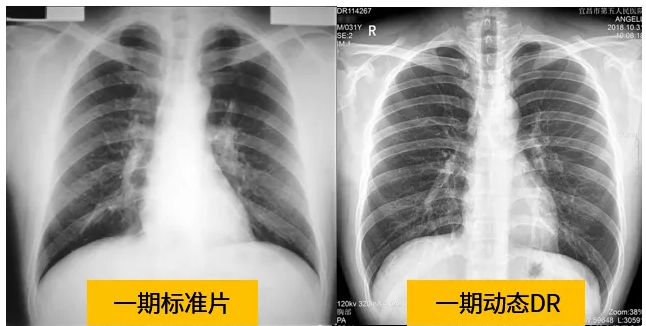

動(dòng)態(tài)dr的拍攝效果圖

動(dòng)態(tài)DR技術(shù)與普通DR單截面診斷的不同就是在操作過程中,可以隨時(shí)切換成透視模式,透視/攝片模式實(shí)時(shí)切換,對陰影進(jìn)行多角度動(dòng)態(tài)的鑒別。實(shí)時(shí)點(diǎn)片、實(shí)時(shí)回放、連續(xù)點(diǎn)片等多功能大大的增加了初診的準(zhǔn)確率。在小陰影的形態(tài)和性質(zhì),特別是不規(guī)則小陰影的判斷方面提升,從而達(dá)到提高胸片整體判斷準(zhǔn)確性。

根據(jù)數(shù)據(jù)統(tǒng)計(jì)表現(xiàn),利用動(dòng)態(tài)dr進(jìn)行檢查的話,圖像的質(zhì)量和輻射劑量相對較少。并且動(dòng)態(tài)DR在圖像清晰度和射線穿透力方面完全能達(dá)到塵肺診斷的要求。這種檢查效果的精準(zhǔn)和便捷性是和普通設(shè)備不一樣的,動(dòng)態(tài)DR塵肺攝影應(yīng)用于塵肺疾病診斷中,可以提高檢出率及優(yōu)片率。